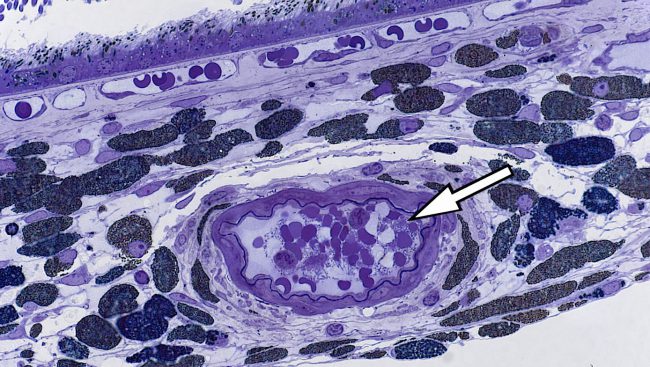

- Photoreceptor toxicity assessment

- Retinal Pigment Epithelium (RPE) toxicity assessment

- Drug pigment interaction assessment

- Photoreceptor toxicity assessment

- Retinal Pigment Epithelium (RPE) toxicity assessment